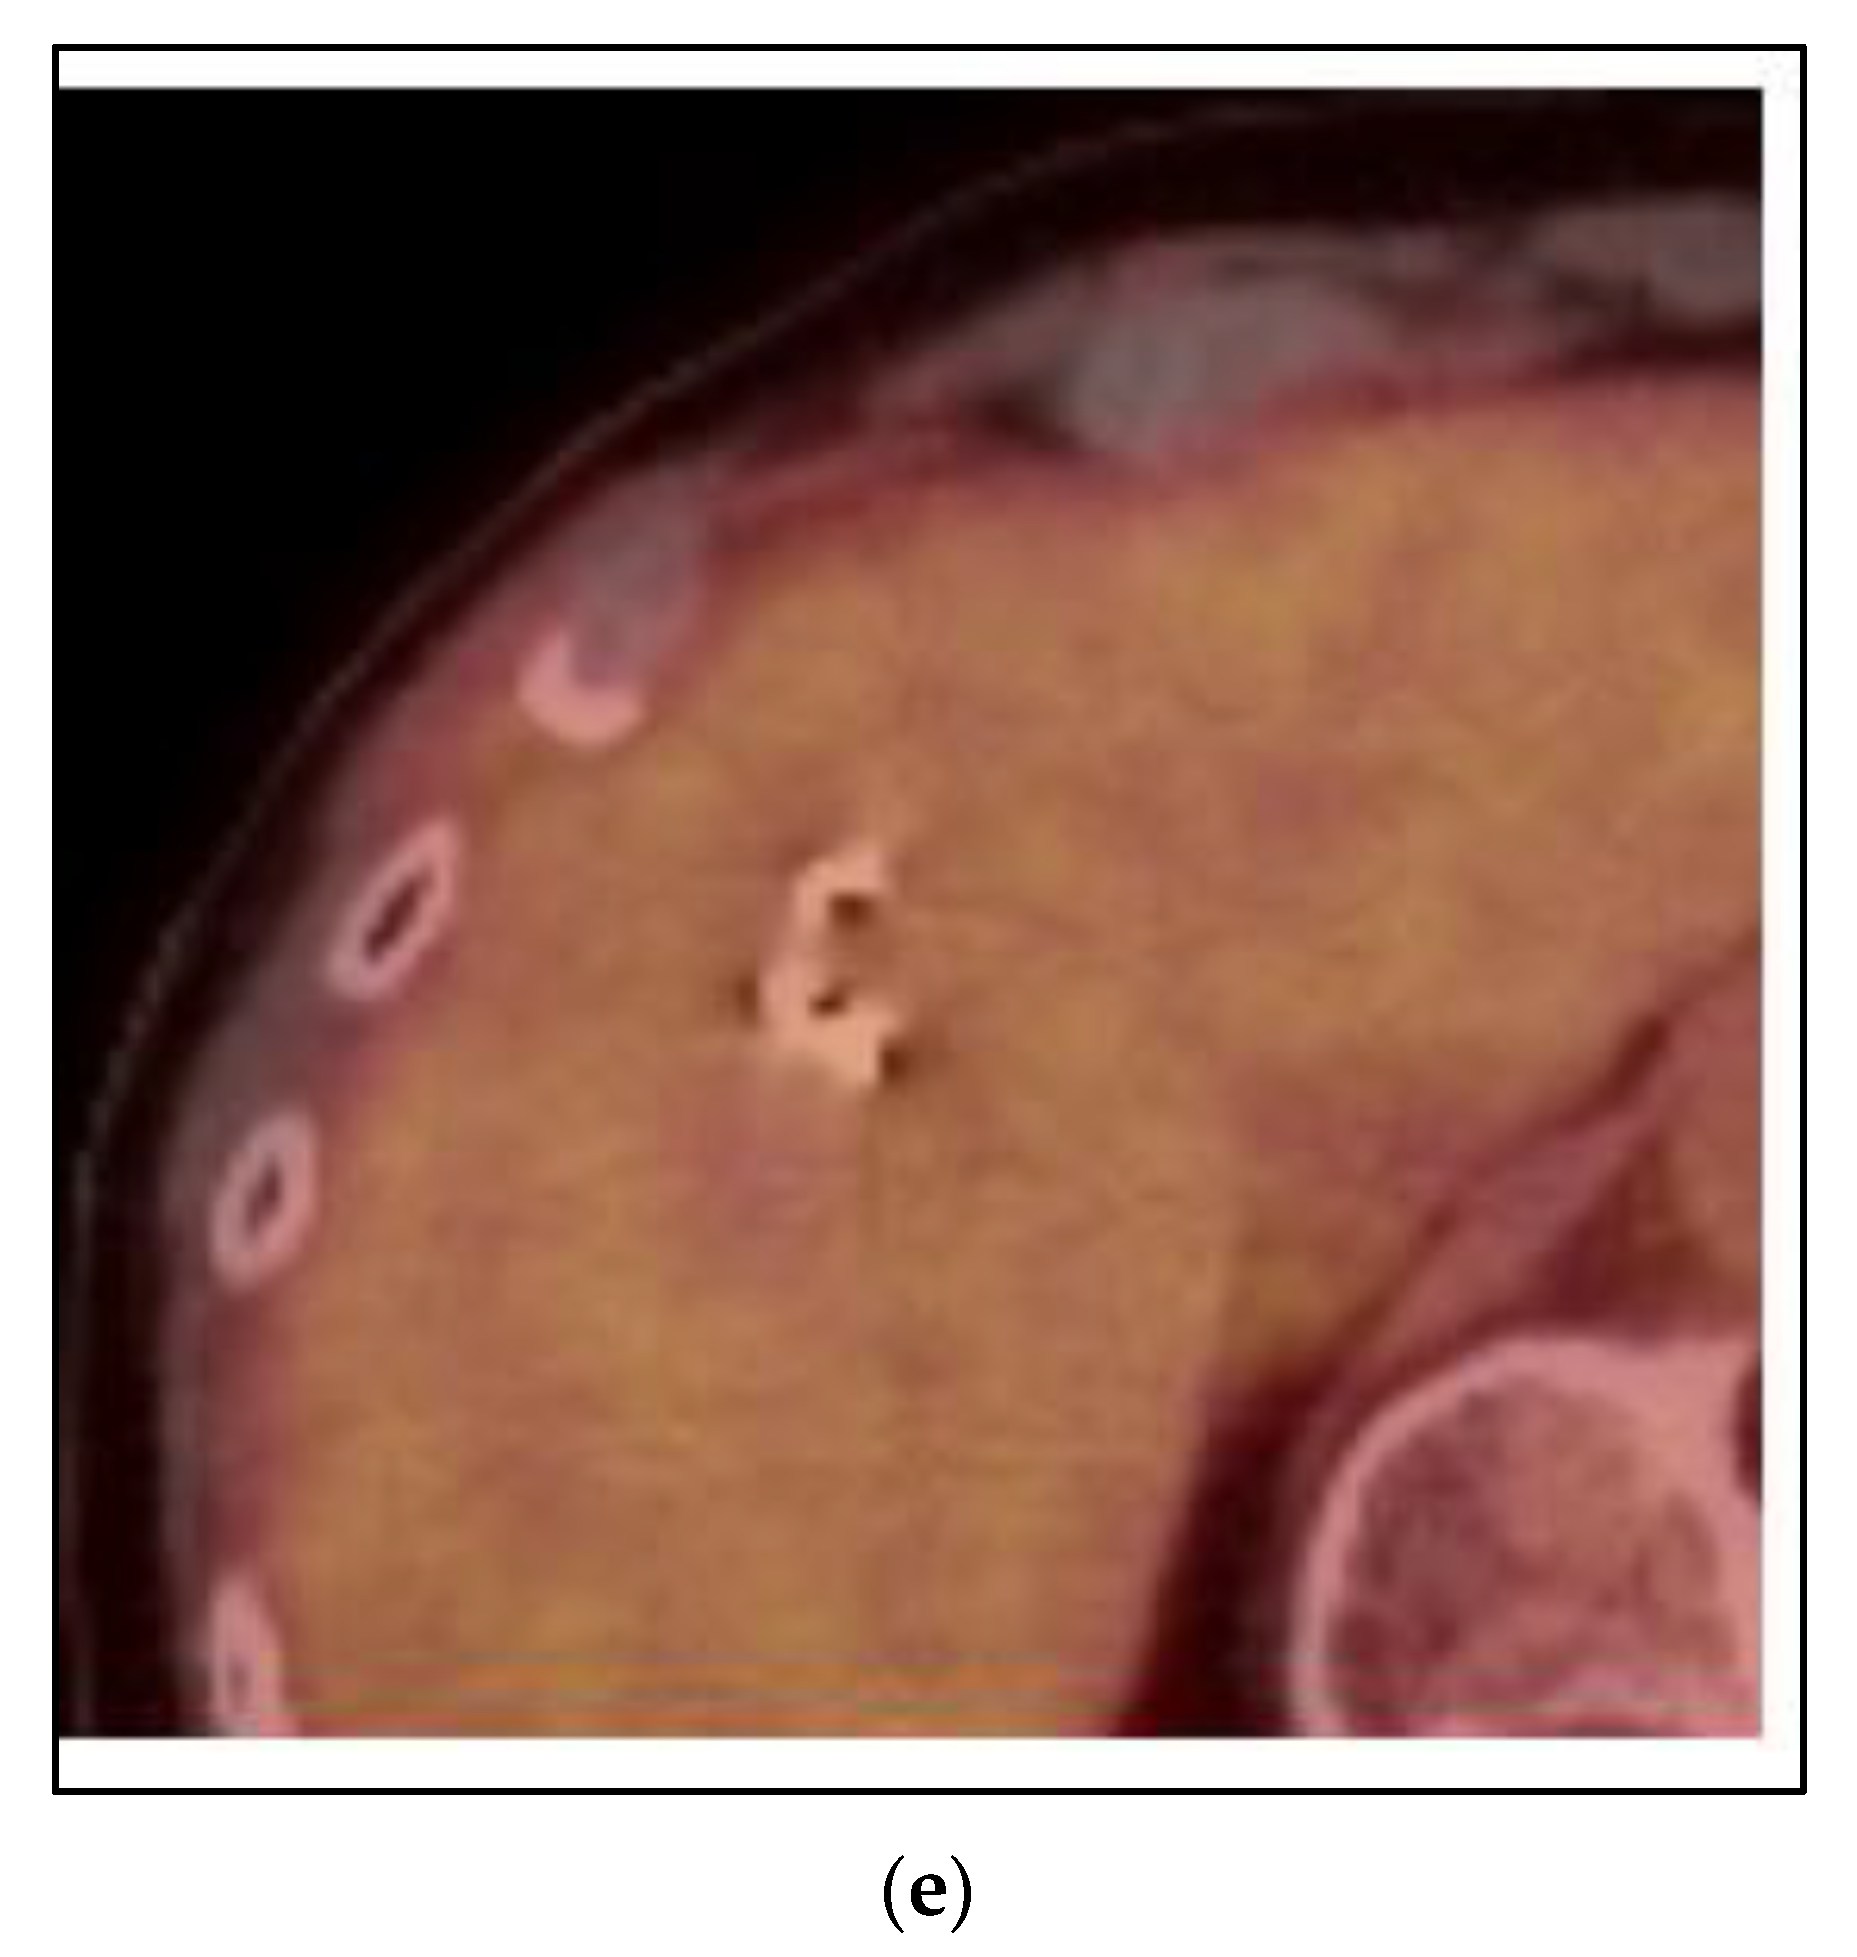

Cases 1–3 have been of synchronous or metachronous oligometastases. In a case of oligoprogression, there can be one or more limited number of sites of metastases that have not responded or progressed on a systemic regimen, while the others remain under control. Figure 5 shows a case of a 45 year old woman who presented with left breast cancer, clinical T1c N1 M0, ER+/PR+/HER2−, stage IB. She had neoadjuvant chemotherapy and bilateral mastectomy with flap reconstruction showing residual disease in the breast and axilla T1c (3) N2a. She was treated with adjuvant tamoxifen. After two years, she developed bone pain, and a bone scan was positive for an extensive number of metastases of the neck, ribs and spine. She was changed to leuprolide, aromatase inhibitor and CDK 4/6 inhibitor. However, within one year, she developed neck pain and an MRI and PET/CT showed a progression of the C1 vertebra. Her other disease was stable. She was treated with SBRT 24 Gy in 2 fractions. She had complete relief of her neck pain and continued on the same systemic therapy.

Figure 5. Case 4: Oligoprogression in the C1 vertebra. A 45-year-old woman presented with oligoprogression at C1 on systemic therapy for metachronous bone metastases. Representative images of the C1 metastasis on PET/CT (a) and MRI (b). (c) A colorwash image superimposed on a radiation planning CT showing the dose from SBRT to the C1 vertebral metastasis 24 Gy in 2 fractions with photon IMRT.